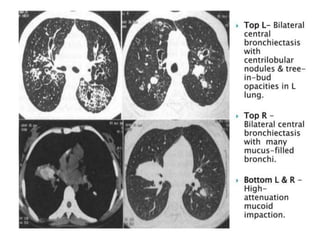

HRCT Finding :-

• Bronchiectasis is classically cylindric and proximal

(central),occurring within the proximal two-thirds of the

lung.

• Widespread proximal cylindrical bronchiectasis (mostly of

upper lobes)

• Bronchial wall thickening

• Mucous plugging

• Atelectasis

• Peripheral airspace consolidation

• Ground-glass attenuation

• Mosaic perfusion

• Air trapping

Central bronchiectasis and mucoid impaction

(finger-inglove sign), characteristic of ABPA.